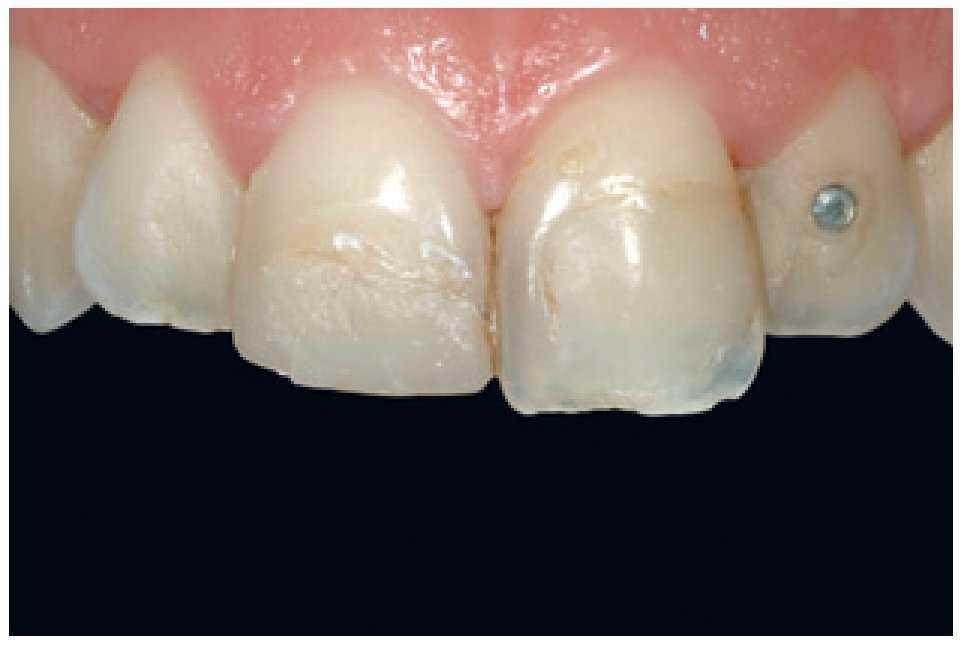

La paciente era una mujer de 32 años de edad con elevadas exigencias estéticas que acudió a la clínica necesitando un tratamiento de urgencia, tras haber pegado ella misma un fragmento de composite con cianoacrilato a una restauración preexistente en el diente número 11. No mencionó dolor ni hipersensibilidad térmica, pero sí se quejó de un leve sangrado gingival esporádico. La exploración clínica (figura 32) reveló la presencia de una serie de restauraciones de resina en los dientes 11, 21 y 22, incongruentes en términos de perfil de emergencia, color y grado de acabado, con márgenes teñidos infiltrados por caries secundaria. Más importante que esto, las restauraciones eran estética y anatómicamente deficientes. La exploración de los tejidos gingivales reveló la presencia de una gingivitis marginal causada por la deficiente higiene de la paciente y un gran acúmulo de placa bacteriana. Aún así, el aparato periodontal aparentemente estaba en buen estado.

Figura 32 Imagen previa al tratamiento que muestra el intento de la paciente de pegar un fragmento fracturado de composite en el diente número 11, alteraciones de las restauraciones existentes y evidencia del grado de contaminación por placa bacteriana.